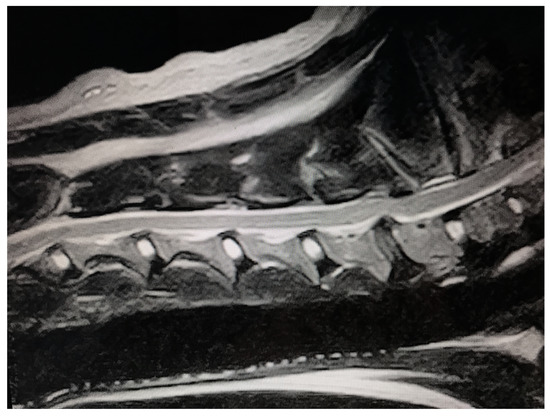

3.2. Preoperative Assessment